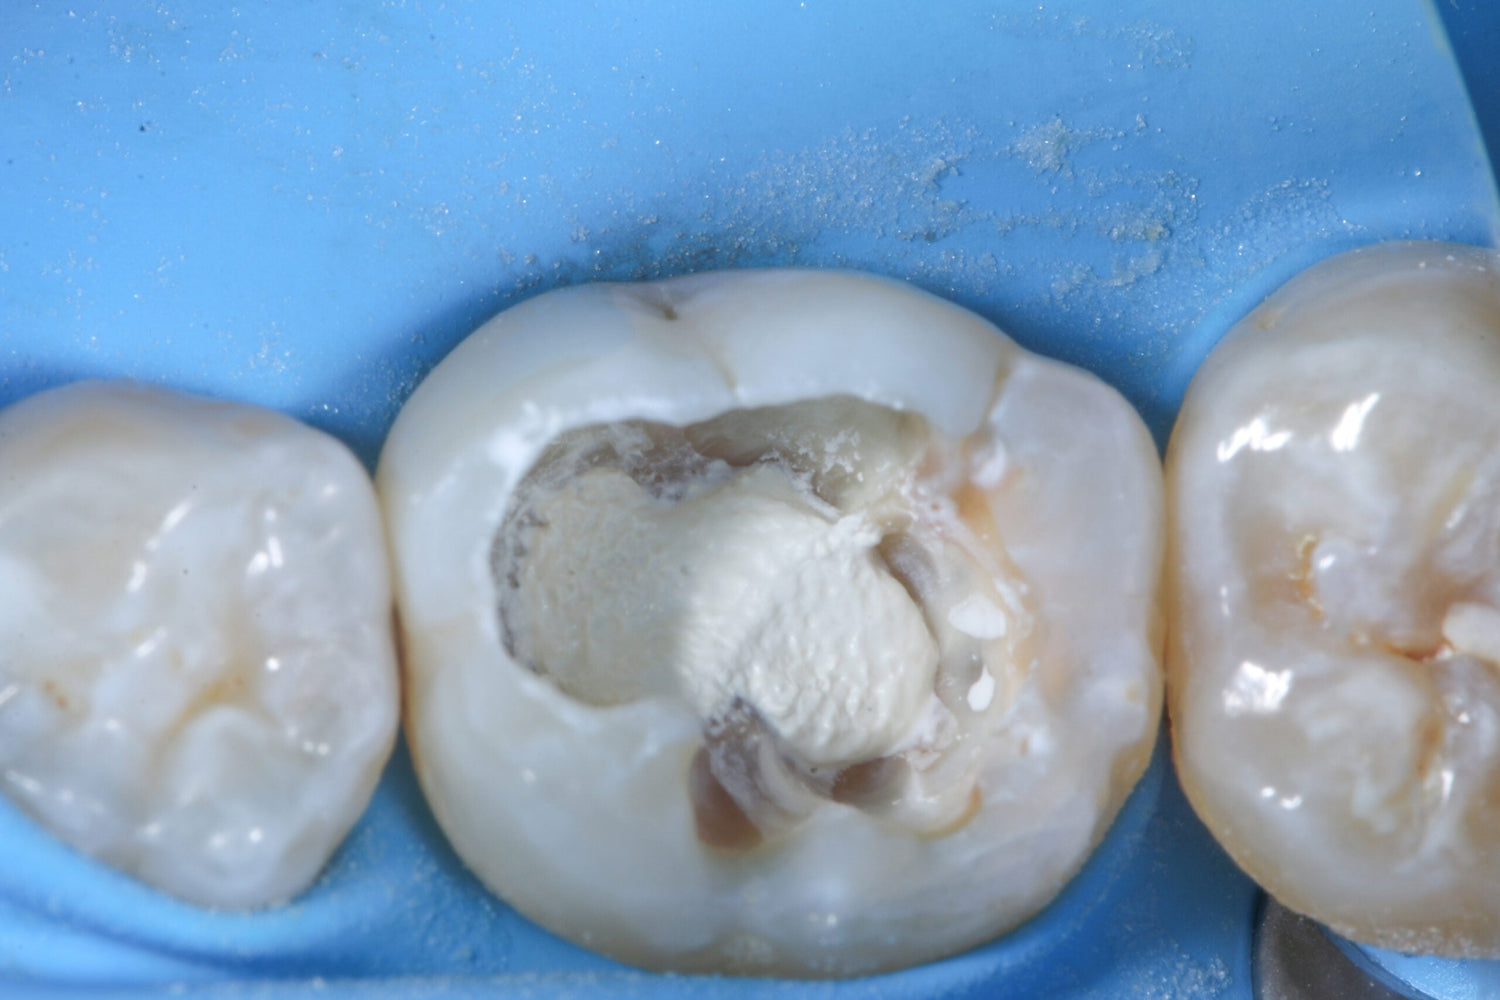

As the affected molar already had a filling, the existing restorative material was removed with a diamond bur. He then eliminated the secondary caries using an EndoTracer, switching to a hand instrument for precise finishing of the remaining tooth structure.

Once all secondary caries had been removed, a partial pulpotomy of the infected but still vital pulp was carried out. An access cavity was created with a bur to reach the mesial pulp horn. To open the horn, Benjamin used a sterile instrument to minimise infection risk. The pulp horn was removed with millimetre accuracy, ensuring an even surface suitable for the later placement of Komet BioRepair putty.

The site was then thoroughly disinfected by continuous rinsing with sodium hypochlorite. Prior to sealing, the enamel was carefully etched to improve adhesion.

Benjamin applied the Komet BioRepair putty to cover the prepared area and seal the cavity. To optimise bonding, he used a self-adhesive flow material over the BioRepair and sandblasted the region.

The stages of a partial pulpotomy in pictures